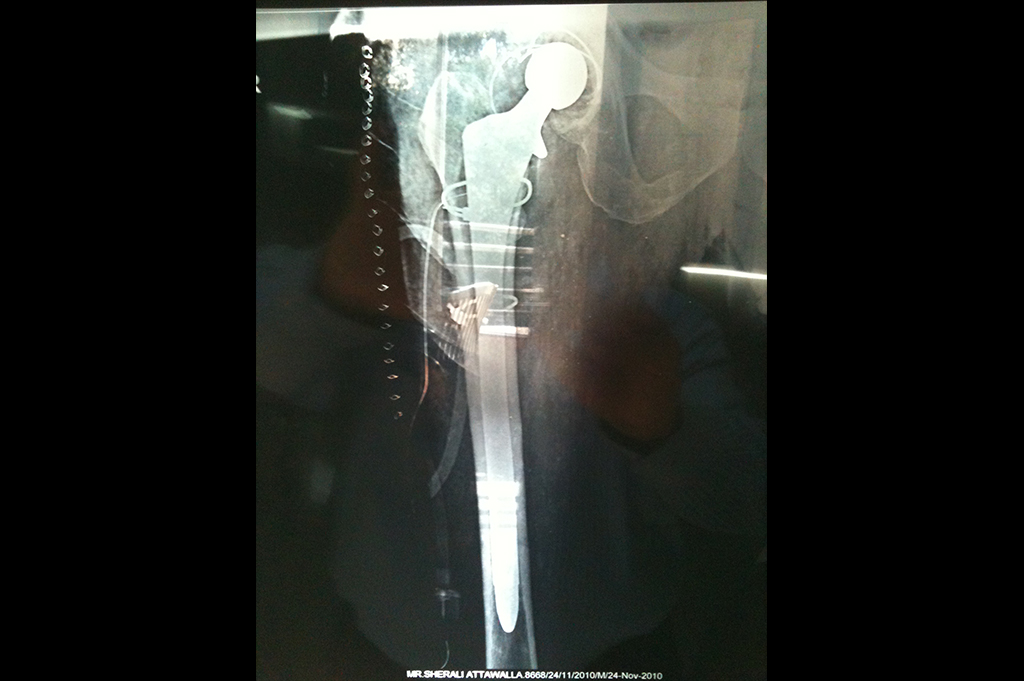

Periprosthetic Fracture THR